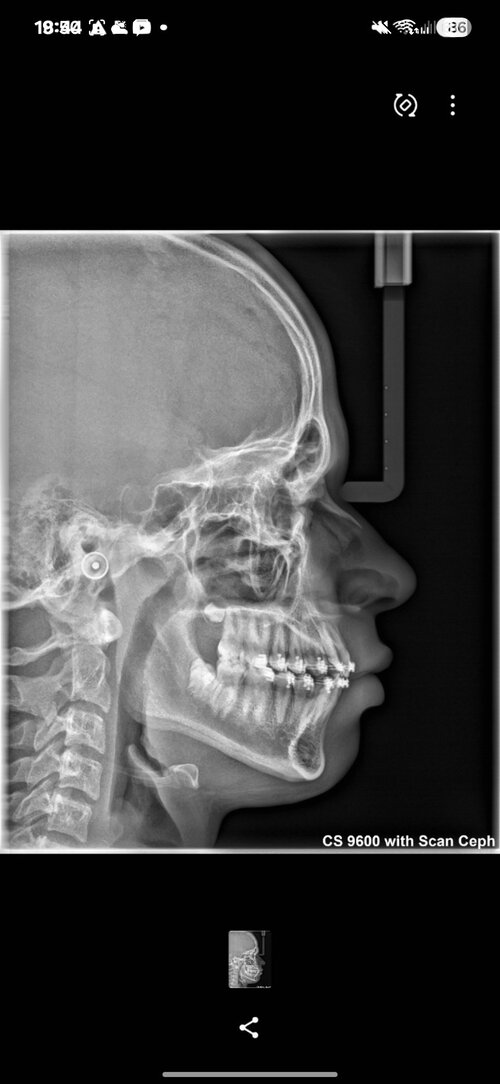

Hi everyone, how are you? I have facial asymmetry — my right side is more drooped/weaker. I won’t drag this out, so I’ll list a few symptoms:

I feel like the right side of my palate is slightly higher, while the left side is slightly lower and wider. I also feel that my lower second molar is a bit inward (when I touch it with my tongue). I probably have bruxism as well — when I open my mouth wide, I notice a difference in my TMJ movement, especially on the right side.

I also feel like my lower teeth are more inward (I’m not sure how to explain it exactly). I’d like to know the best way to fix this. I’ll send some photos and my cephalometric analysis, If you could please use simpler English, I would appreciate it, as I am Brazilian and it's difficult to translate(Note: I also feel a slight muscular difference when touching my face.)

I feel like the right side of my palate is slightly higher, while the left side is slightly lower and wider. I also feel that my lower second molar is a bit inward (when I touch it with my tongue). I probably have bruxism as well — when I open my mouth wide, I notice a difference in my TMJ movement, especially on the right side.

I also feel like my lower teeth are more inward (I’m not sure how to explain it exactly). I’d like to know the best way to fix this. I’ll send some photos and my cephalometric analysis, If you could please use simpler English, I would appreciate it, as I am Brazilian and it's difficult to translate(Note: I also feel a slight muscular difference when touching my face.)

Screenshot_20260405_162426_Gallery.jpg1.3 MB · Views: 0

Screenshot_20260405_162426_Gallery.jpg1.3 MB · Views: 0 -